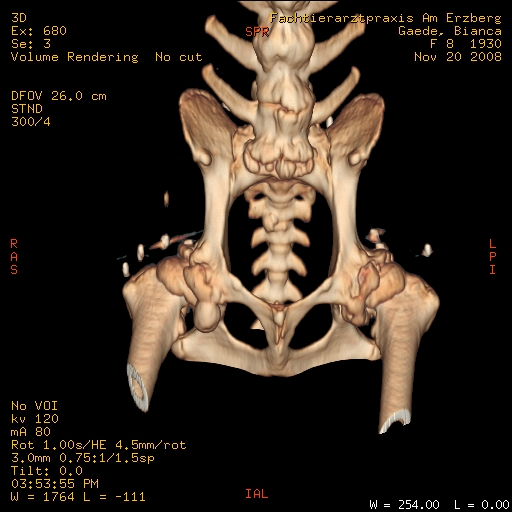

Nachstehend die Aufnahmen der im November gemachten CT, dort kann man sehen, wie krass die Hüfte entartet ist und wieviel Arthrosen sich gebildet haben, für mich waren es die totalen Horrorbilder, vor allem, wenn ich an die ersten Röntgenaufnahmen ihrer Hüfte denke, wo mein TA auch die Möglichkeit des Einschlafens erwähnt hat, weil er meinte, daß Bibo mit dieser Hüfte kein Leben ohne Schmerzen führen kann.Externer Inhalt www.fotos-hochladen.netInhalte von externen Seiten werden ohne deine Zustimmung nicht automatisch geladen und angezeigt.Externer Inhalt www.fotos-hochladen.netInhalte von externen Seiten werden ohne deine Zustimmung nicht automatisch geladen und angezeigt.Externer Inhalt www.fotos-hochladen.netInhalte von externen Seiten werden ohne deine Zustimmung nicht automatisch geladen und angezeigt.Externer Inhalt www.fotos-hochladen.netInhalte von externen Seiten werden ohne deine Zustimmung nicht automatisch geladen und angezeigt.Externer Inhalt www.fotos-hochladen.netInhalte von externen Seiten werden ohne deine Zustimmung nicht automatisch geladen und angezeigt.Externer Inhalt www.fotos-hochladen.netInhalte von externen Seiten werden ohne deine Zustimmung nicht automatisch geladen und angezeigt.Externer Inhalt www.fotos-hochladen.netInhalte von externen Seiten werden ohne deine Zustimmung nicht automatisch geladen und angezeigt.Externer Inhalt www.fotos-hochladen.netInhalte von externen Seiten werden ohne deine Zustimmung nicht automatisch geladen und angezeigt.Externer Inhalt www.fotos-hochladen.netInhalte von externen Seiten werden ohne deine Zustimmung nicht automatisch geladen und angezeigt.Bibo ist inzwischen 8 Jahre alt und wir hatten wirklich schlimme Zeiten, weil sie auch schwere Spondy (wie man auch auf den Bildern erkennen kann) und inzwischen auch Cauda Equina hat (macht ihr aber zum Glück keine Probleme). Durch die Spondy habe ich im September/Oktober 2007 gedacht, daß ich sie einschläfern lassen muss, weil ich ihre Schmerzen nicht mehr ertragen konnte. Aber ich hatte sehr viel Glück, durch das Forum vor allem und konnte Bibo im November 2007 eine Goldakku machen lassen.

Hier die CT-Bilder: